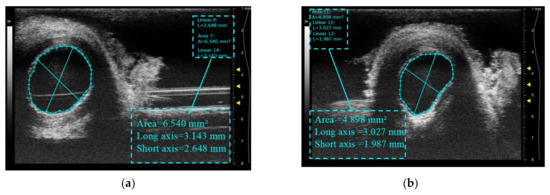

The integrated probe prototype is depicted in Figure 1a, which displays a single-element imaging probe positioned within the central hole of a spherical-focused therapeutic probe. The therapeutic probe operates at a center frequency of 4.5 MHz, while the imaging probe operates at 12 MHz. Two probes were fixed to the mechanical structure by connectors. Compared to the therapy system guided by a linear array B-mode imaging probe, the volume is significantly reduced, which is depicted in Figure 1b.

Figure 1.

Prototype probe for integrated ultrasound imaging and therapy: (a) system guided by a single-element imaging probe; (b) dimensional comparison, the right is a system guided by a B-mode imaging probe.